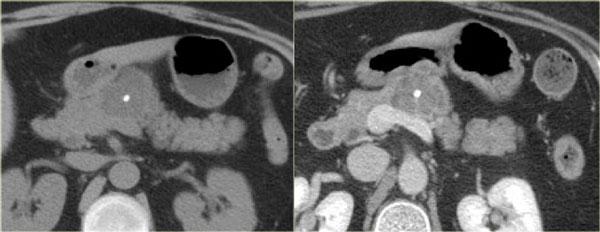

Một ví dụ khác về u nang tuyến thanh dịch (Hình).

Hình ảnh sau tiêm thuốc cản quang bên phải cho thấy tổn thương giảm tỷ trọng với vôi hóa trung tâm ở thân tụy và ngấm thuốc nhẹ của các vách ngăn.

Lưu ý rằng trên CT rất khó nhận ra bản chất dạng nang của các tổn thương này và có thể nhầm lẫn với ung thư biểu mô tuyến tụy.

MRI sẽ dễ dàng thể hiện bản chất dạng nang của các tổn thương này (hình).

Chuỗi xung T2W với xóa mỡ (fatsat) thể hiện rõ tổn thương tăng tín hiệu dạng thùy múi với sẹo trung tâm, đây là hình ảnh đặc trưng của SCN.